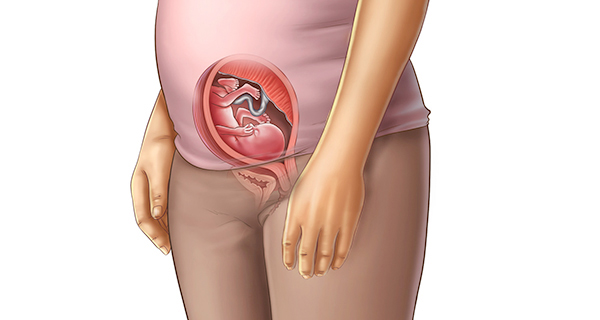

وضعیت مادر در هفته هفدهم بارداری

در هفته هفدهم شکم مادر بزرگتر از قبل شده و هرچه حاملگی پیشرفت میکند رحم دایرهای تر و گردتر میشود و شکلی شبیه تخممرغ میگیرد که چون رشد طولی رحم سریعتر است به این شکل درمیآید. در طول این مدت ضخامت جفت به 54.2 سانتیمتر میرسد و رحم در 5 سانتیمتری زیر ناف است. همین قضیه باعث میشود که به اجزای شکم فشار وارد شود تا به کنار بروند و جای کافی برای رحم وجود داشته باشد.

همانطور که گفته شد در این هفته رحم بزرگتر میشود و به همین دلیل به اجزای داخلی شکم فشار بیشتری وارد میشود. رباتی که سر استخوان ران قرار دارد و به آن رباط گرد گفته میشود از دو طرف رحم به سمت دیواره لگن کشیده میشود و چون رحم در طول دوره بارداری بزرگتر میشود رباطها هم قطورتر و طویلتر میشوند و کشش زیادی شامل حال آنها میشود.